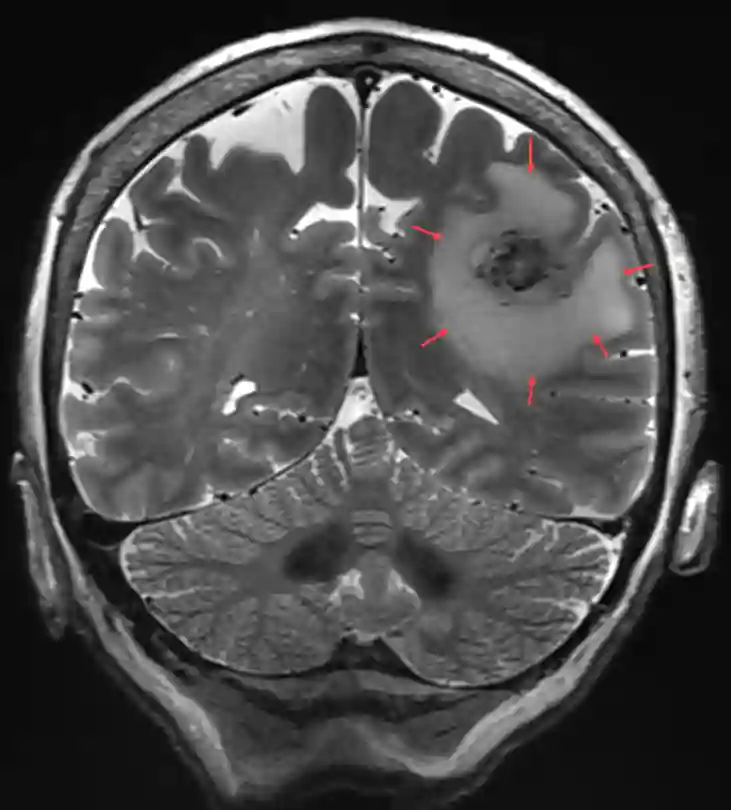

Bildgebung

Bildgebend lässt sich ein vasogenes Hirnödem optimal in einer T2 MRT Bildgebung darstellen. In der T2 Sequenz zeigt sich ein vasogenes Hirnödem hyperintens.